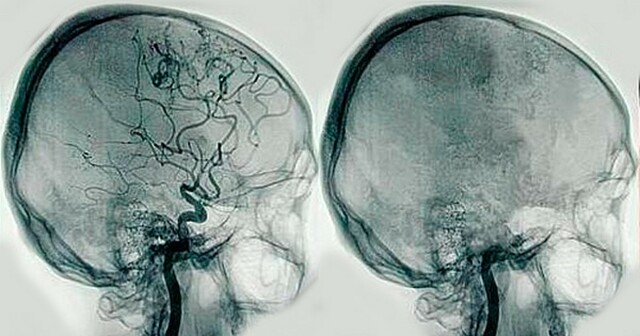

• origen de la angiografia

origen de la angiografia

se logra la primera pielografia intravenosa usando uroselectan (yodo organico) dando paso a un nuevo campo. La Angiografia.